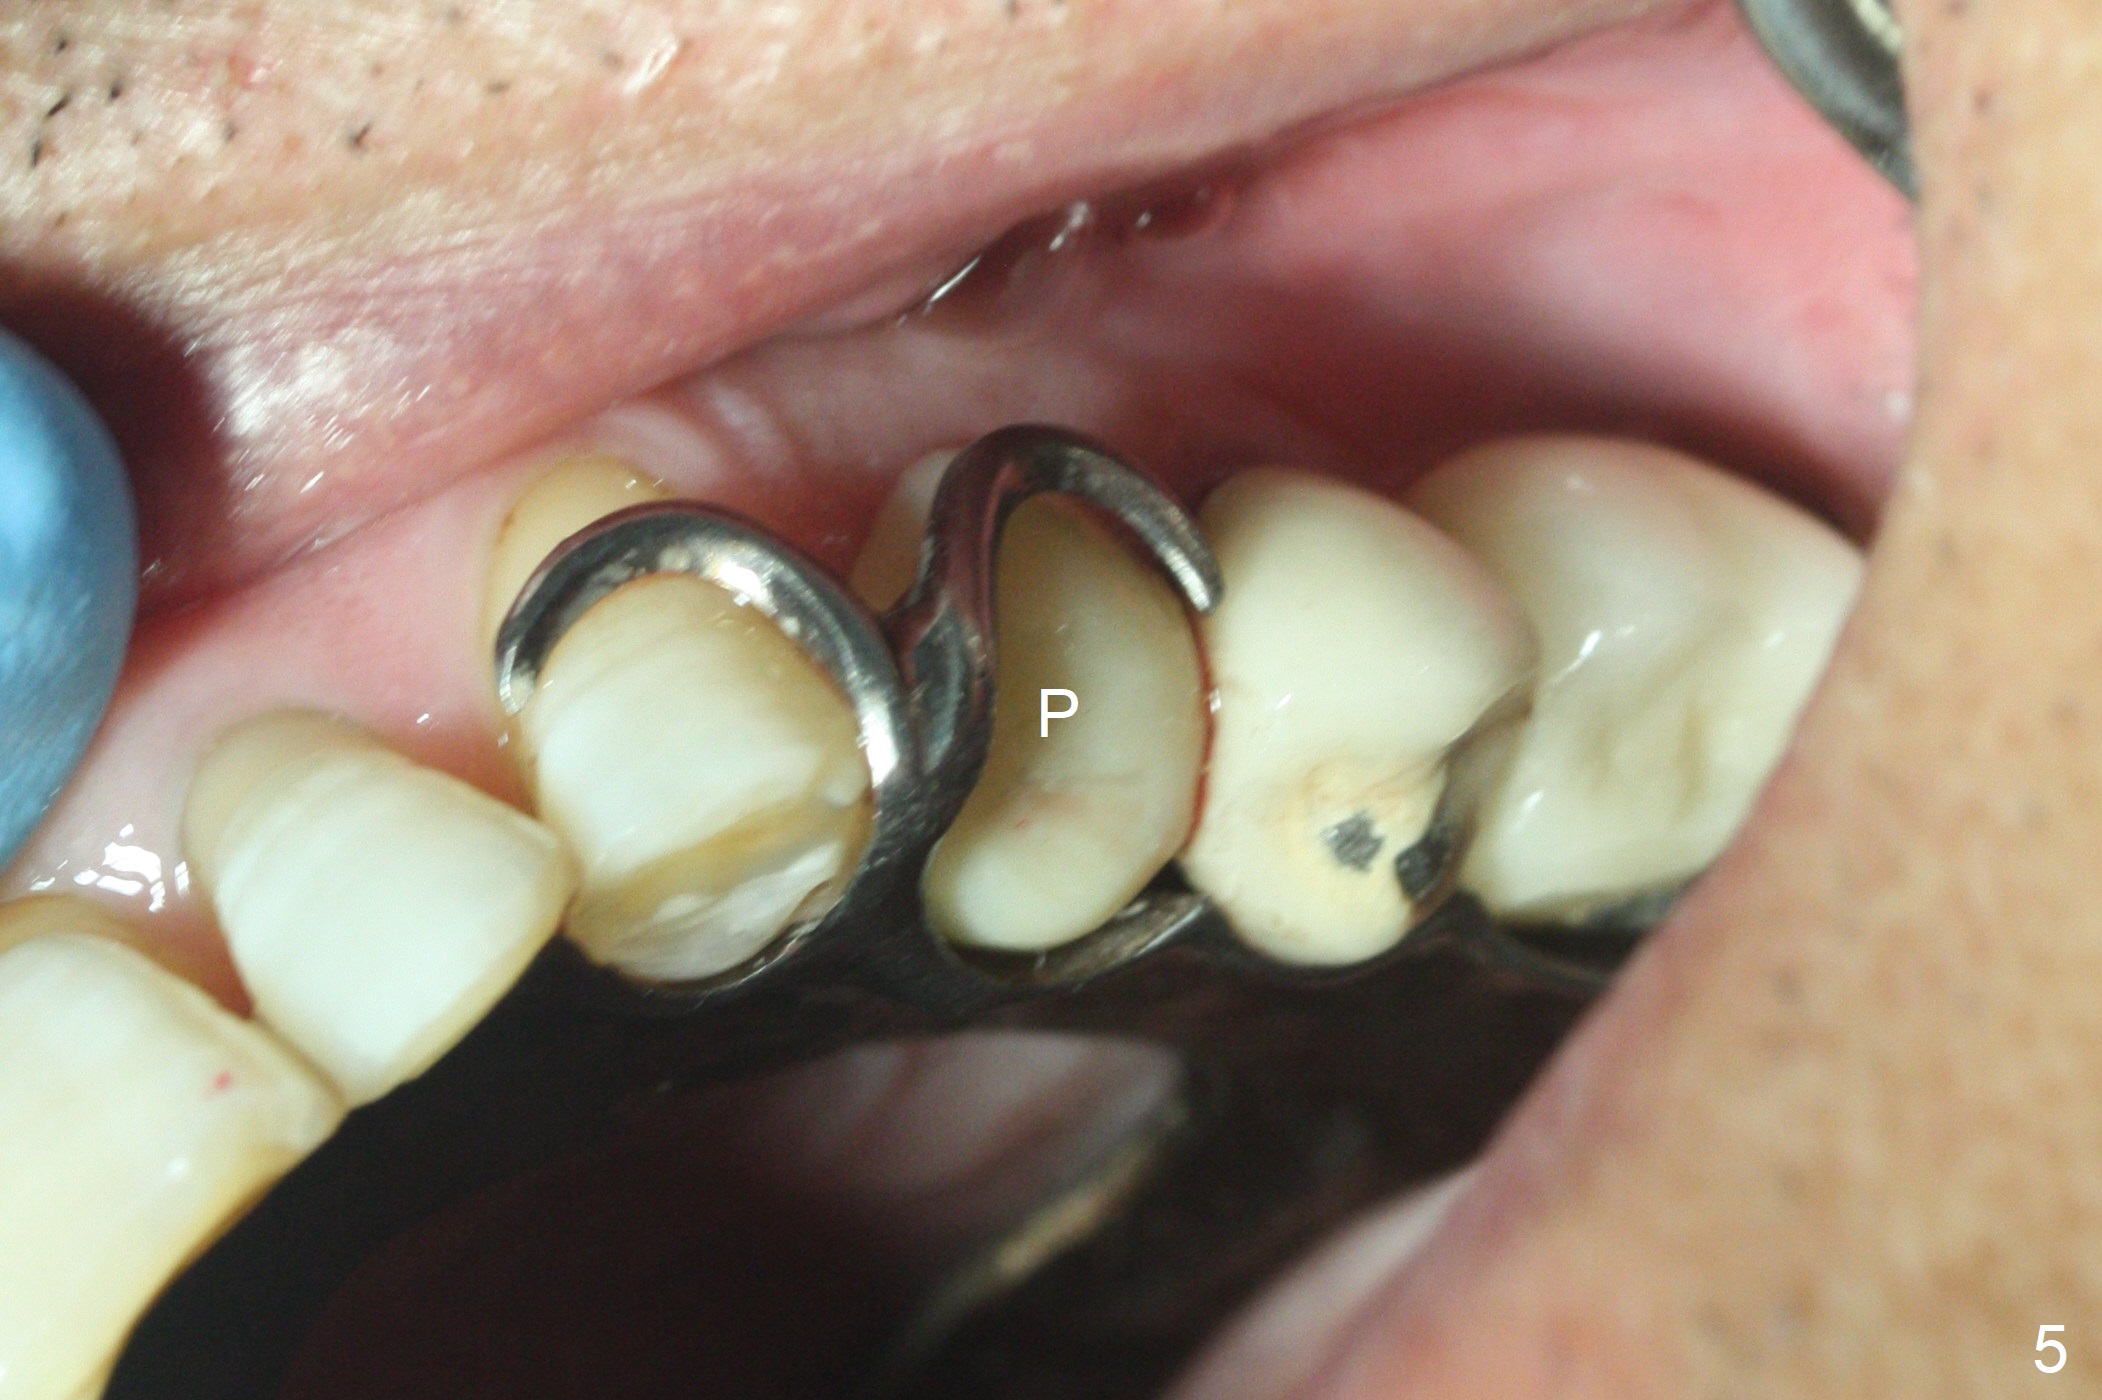

After extraction of the oval-shaped residual roots at #12 (Fig.1), osteotomy is initiated in the palatal socket for 18 mm; since the root of the canine curves distal (Fig.2 red dashed line), the osteotomy cannot afford to move mesial and extend more apical.  A 3.8x15 mm implant is placed with > 50 Ncm (Fig.3).  With immediate placement of a 4.5x4(3) mm abutment, an immediate provisional is fabricated to close the sockets (Fig.4 P).  The provisional has clearance from the RPD clasps (Fig.5).  In fact the implant could be longer, as shown by immediately postop panoramic X-ray (Fig.6).  The implant seems to be osteointegrated 3 months postop (Fig.7).  The tooth #13 is symptomatic with caries (Fig.8 C) 7 months post #12 crown cementation; the #13-15 FPD dislodges.  The upper left quadrant is cold and hot sensitive 2.5 months post RCT (Fig.9); although there is mild percussion at #13, pulpal test shows that the tooth #15 has lingering pain.  The FPD was recemented temporarily after RCT; it cannot be removed.  The implant crown has been loose for several months during the pandemic before he returns 2 years 7 months post cementation.  In fact the abutment has been not seated completely (from Fig.3 to 9).  The crown/abutment is removed from the mouth; the crown is sectioned and separated from the abutment; the latter is reseated, but incompletely (Fig.10 <).  With suspicion of the mesial crestal contact, profile drills 4.6 and 5.5 mm are used without effect.  A new (old probably being worn) and longer (easy to turn in the narrow space) abutment is finally seated completely (Fig.11 (no gap)).  After occlusal adjustment, abutment level impression is taken for a new crown.